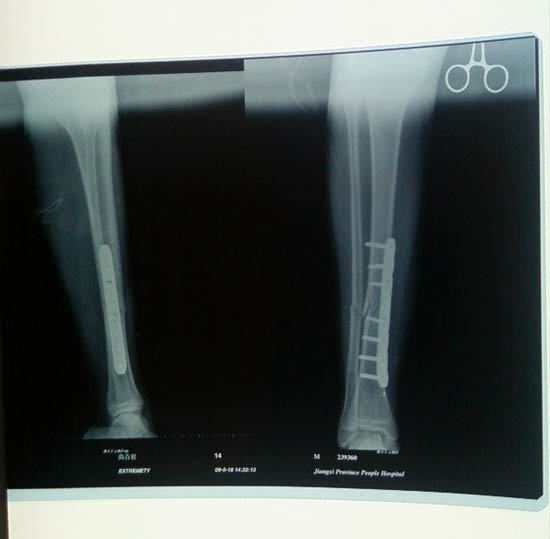

胫骨骨折微创切口钢板内固定图例

小张入院后骨二科与病人及家属多次沟通,告知如采取夹板、石膏固定非手术治疗,骨折复位不可能很好,且病人患肢活动受限膝关节、踝关节易僵硬;治疗时间长影响病人学习。而运用小切口复位钢板固定,手术创伤小、术后疤痕小,病人可早期活动,对关节功能恢复好。小张及家属经考虑后选择了微创手术钢板内固定治疗,术后小张恢复的很快,并且没耽搁学习。

微创手术优点:微创手术具有创伤小、疼痛轻、恢复快的优越性。手术采用多个小切口,骨折一端切约3cm切口置入钢板,外加1-1.5cm小切口上螺钉;闭合复位骨折,钢板置于骨膜外,骨膜剥离少骨折端血运好,所以骨折愈合快;皮肤创口小,疤痕小。小切口疼痛轻,患者疼痛感小。术后病人恢复快,骨折肢体行钢板内固定后得到即刻稳定,肢体关节可以活动;相当使用夹板、石膏、牵引治疗引起关节僵硬,微创手术钢板内固定使术后恢复时间缩短。住院时间短:一般情况下手术后24小时可下床, 7-10天出院,费用相对降低。手术切口小出血不多。